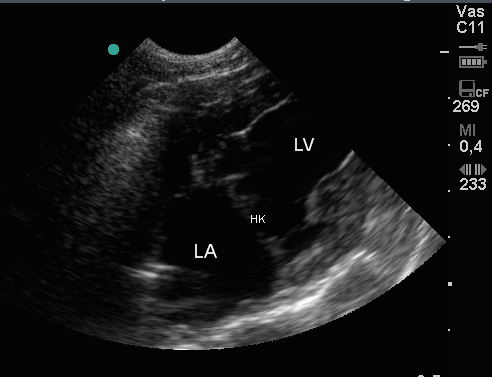

Die oberen beiden US-Bilder zeigen eine Technik, die es dem Untersucher ermöglicht, die Effizienz der Herzleistung darzustellen.

Das unterste Bild zeigt die geschlossene Herzklappe (HK)zwischen der linken Vorkammer (LA) und Kammer (LV).